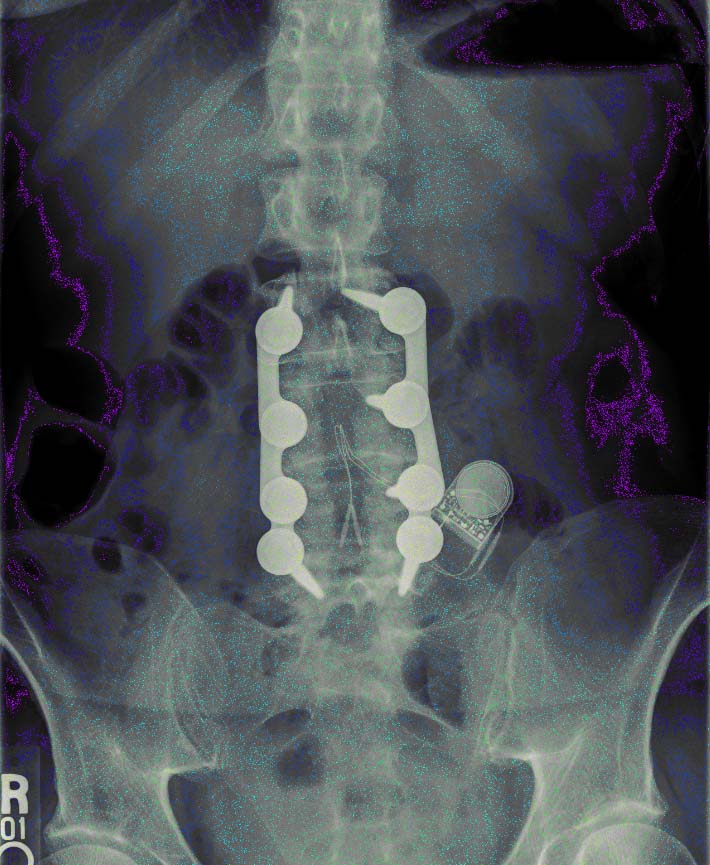

The Wonders of Modern Medicine and Computer Graphics

check out the battery...it's no longer doing anything, but my ashes will be toxic waste.